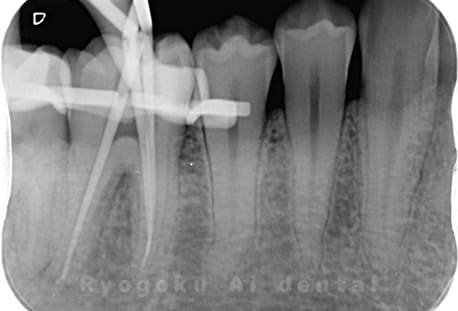

Case07

- 原因

- 慢性根尖性歯周炎(16・17・15部)

- 治療内容

- マイクロエンド(3歯分)

- 治療費用

- 308,000円(3歯分)※被せ物を除く

右上の違和感が取れないとのことで来院された患者さんです。ファイルという器具が歯の根の中で折れていることを説明し、マイクロスコープを使用した根管治療を提案し、治療を行いました。折れたファイルも取り除くことができ、現在の経過は良好です。

<リスク・副作用>

術後は痛み、腫れ、痺れなどの副作用が生じる場合があります。症状が再発する可能性があります。